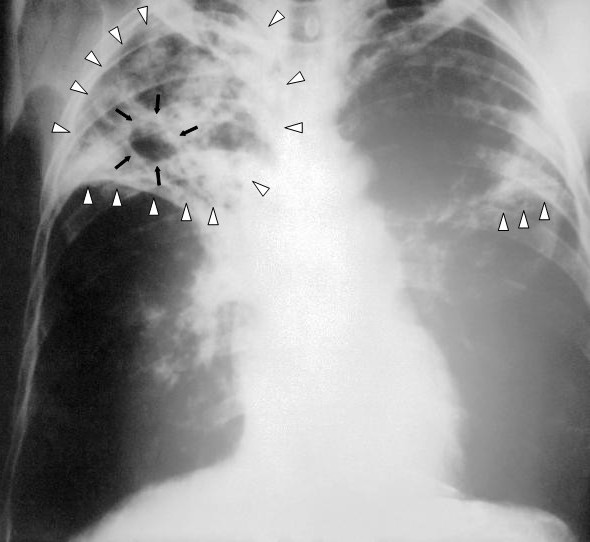

- Тканинні рубці на легенях